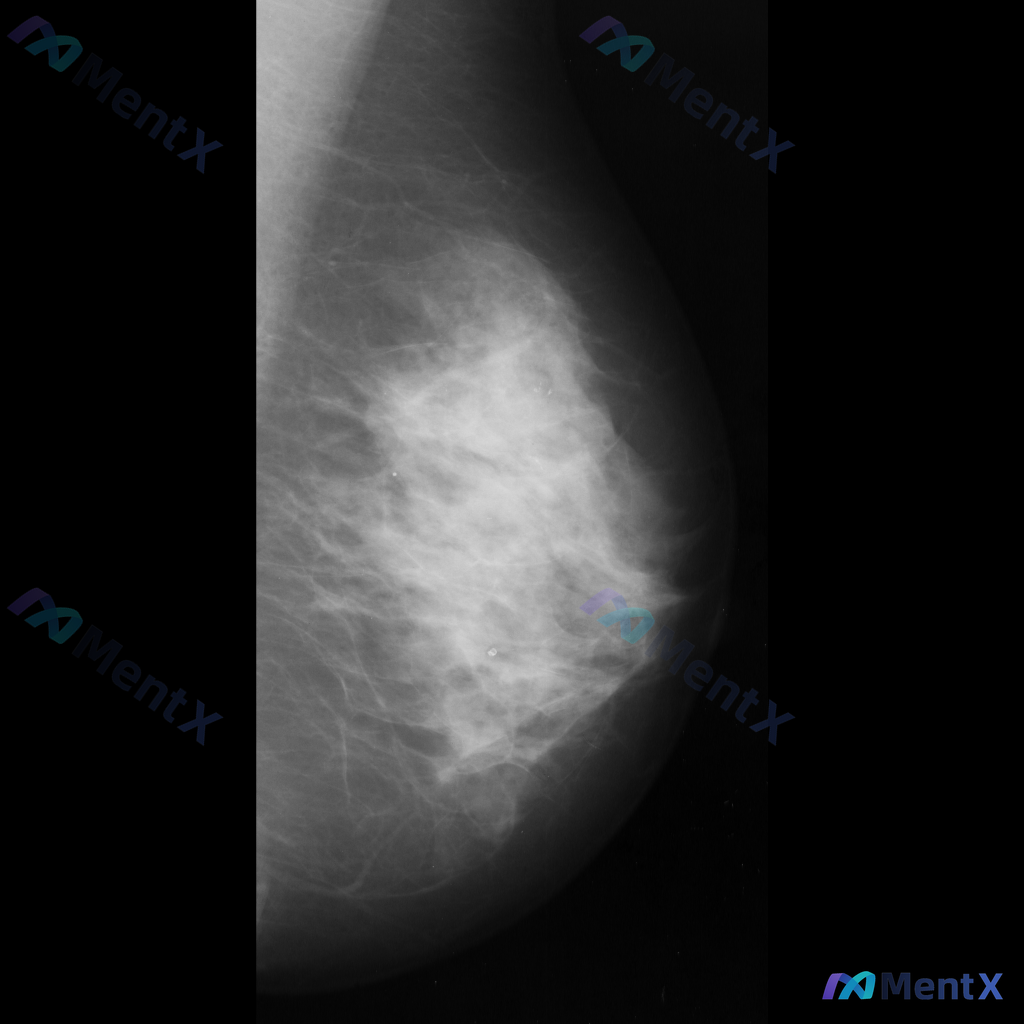

整理到一张乳腺钼靶的读片资料,想和大家一起讨论一下。 图像里能看到两处比较明确的异常: - 乳腺中下部有一个不规则、毛刺状的高密度肿块,周围还有结构扭曲的表现 - 乳腺上部还有一个类圆形的高密度肿块,形态相对规则一些 背景是不均匀致密型的乳腺组织。 单看这组图像表现,大家会优先往哪个方向考虑?